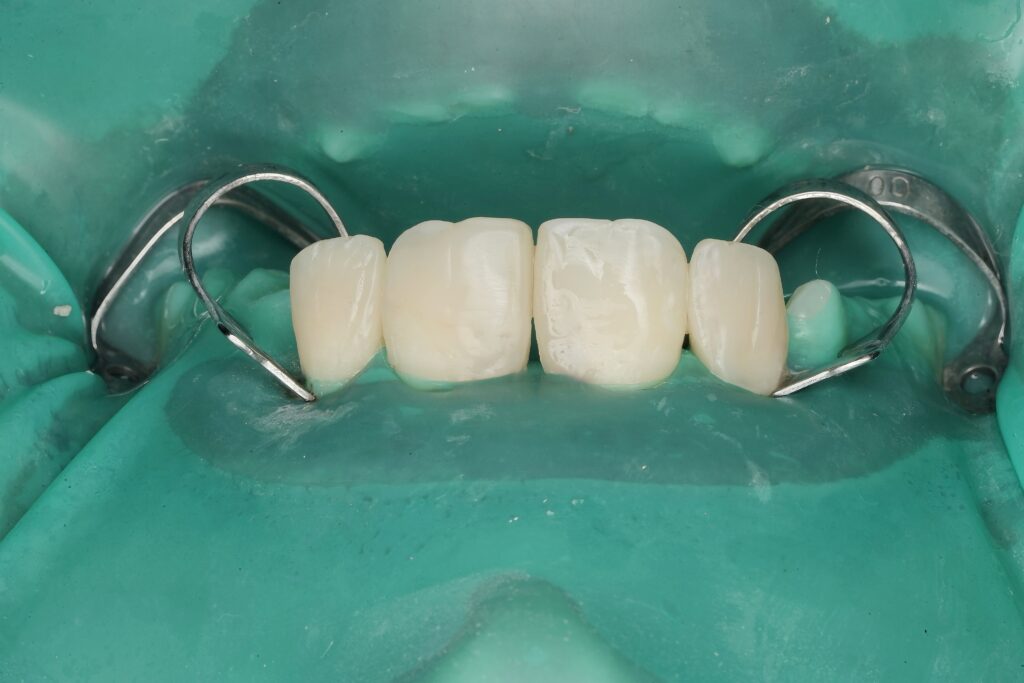

Step 1 – Isolation

- Full rubber dam isolation applied

- Proper retraction ensured clean adhesive field

- Isolation critical to prevent contamination and ensure bond longevity

Step 5 – Composite Layering Technique

A biomimetic layering approach was used:

- Palatal shell first to establish framework

- Dentin body shade to create opacity

- Enamel layer for translucency

- Subtle characterization for depth

Each increment was sculpted anatomically rather than bulk-filled, restoring natural line angles and surface morphology.